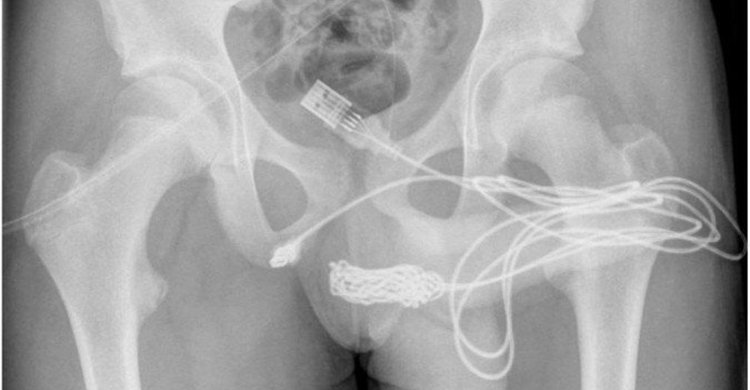

Um adolescente de 15 anos precisou passar por uma cirurgia após enfiar um cabo USB no pênis. O caso ocorreu em Londres, no Reino Unido, e foi divulgado por um artigo científico publicado na revista “Urology Case Reports”.

O jovem, que não teve o nome revelado, relatou aos médicos que inseriu um cabo USB, utilizado para carregar aparelhos celulares, na uretra para medir o comprimento do pênis. Ao perceber que havia prendido o cabo no membro, ele tentou removê-lo manualmente, mas acabou piorando a situação e prendendo as duas pontas do objeto na uretra.

O adolescente foi com a família ao hospital mais próximo, mas tentativas manuais ou endoscópicas de remoção não foram eficientes porque havia um nó no cabo USB.

Ele foi então encaminhado ao University College Hospital London, onde há tratamento especializado e cirurgias urológicas. Os médicos precisaram realizar uma uretrostomia penoescrotal, onde é feito um corte entre a genitália e o ânus do paciente. O cabo foi cortado e retirado através de um meato uretral externo.

O adolescente recebeu alta no dia seguinte à cirurgia. Ele precisou usar cateteres suprapúbicos para drenar a urina por duas semanas. Segundo os médicos, o jovem não terá sequelas.

Repórter Ceará – Correio Braziliense (Foto: Calum Grant/Urology Case Reports)